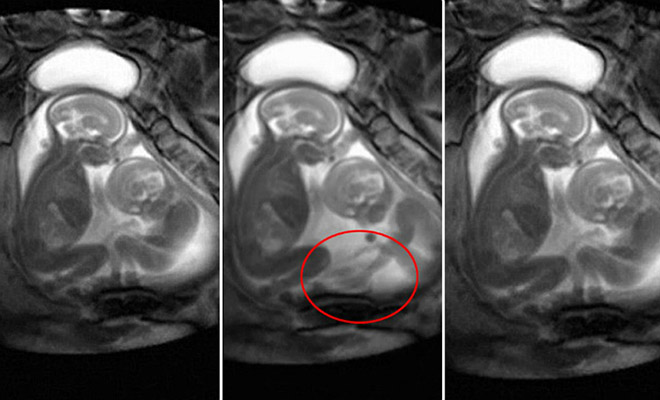

Οι μητέρες διδύμων αντιμετωπίζουν υψηλότερο κίνδυνο καρδιακής νόσου τον πρώτο χρόνο μετά τη γέννηση